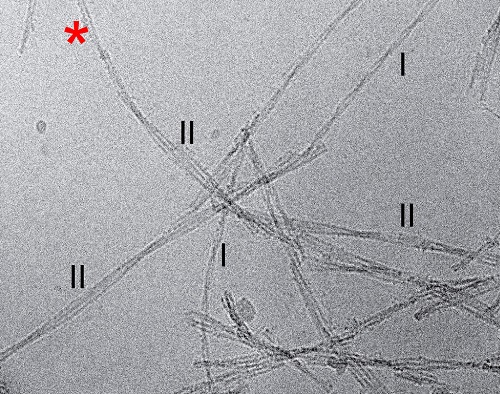

Alzheimer-Auslöser enttarnt25. November 2019 Seitenansicht einer rechts-händigen Aß-Amyloid Fibrille, rekonstruiert aus Fibrillen der Morphologie I (l.). Der Querschnitt einer Fibrill-Ebene zeigt zwei C-förmige Aß-Peptide, die Rücken an Rücken positioniert sind (r.). Die gesamte Fibrille besteht aus mehreren gestapelten Ebenen (r.) (©Kollmer et al., Nature Communications) Wissenschaftlern der Universität Ulm ist es erstmals gelungen, Beta-Amyloid-Fibrillen aus dem menschlichen Gehirn zu isolieren und zu untersuchen. Diese Eiweißfasern stehen im Verdacht, die Alzheimer-Krankheit sowie die Zerebrale Amyloid-Angiopathie mit auszulösen. Dass Morbus Alzheimer mit Proteinablagerungen im Gehirn einhergeht, ist seit vielen Jahren bekannt. Unter Alzheimer-Forschern gelten dabei zwei Proteine, Tau und Beta-Amyloid, als besonders krankheitsverursachend. Diese Eiweiße bilden lange Molekülketten, die sich als Faserklumpen im Gehirn ansammeln. Die genaue Ursache, warum sich körpereigene Proteine krankhaft entwickeln und zu degenerativen Veränderungen des Gehirns führen, ist noch nicht bekannt.Wissenschaftlerinnen und Wissenschaftlern der Universität Ulm ist es jedoch erstmals gelungen, Beta-Amyloid-Fibrillen aus Gewebeproben erkrankter Menschen zu extrahieren und präzise darzustellen. Die Überraschung dabei: Die Fasern unterscheiden sich sehr deutlich von den bisher zur Forschung genutzten, synthetisch erzeugten Fibrillen. Kryo-elektronenmikroskopische Aufnahme von Aß-Amyloid-Fibrillen, welche aus menschlichem Hirngewebe von Alzheimer-Patienten aufgereinigt wurden. Hervorgehoben sind einzelne Fibrillen mit unterschiedlichen Formen (Morphologie I und II). Zu sehen ist außerdem eine Fibrille, welche in unterschiedlichen Bereichen verschiedene Morphologien aufweist (roter Asterisk). (©Kollmer et al., Nature Communications) „Unsere Hauptergebnisse sind, dass wir die Struktur von Beta-Amyloid sichtbar machen konnten, und dass sie sich fundamental von bisherigen Annahmen unterscheidet“, erklärt Prof. Marcus Fändrich, Leiter des Instituts für Proteinbiochemie der Universität Ulm. Zum einen sind die einzelnen Peptide, aus denen sich die Fibrillen zusammensetzen, anders gestaltet als die Exemplare aus dem Reagenzglas, zum anderen sind die nun untersuchten Fibrillen in sich völlig anders verdrillt als die synthetischen Exemplare. „Das ist eine grundsätzlich andere Eigenschaft, die wir so nicht erwartet hatten“, sagt Fändrich.Für ihre Studie untersuchten die Wissenschaftlerinnen und Wissenschaftler Gewebeproben von drei Patienten, in denen sie die gleichen Strukturen fanden. Der Entschlüsselung der Ursachen von Morbus Alzheimer sind die Ulmer Forscherinnen und Forscher damit womöglich einen Schritt näher gekommen. Eine der krankheitsverursachenden Strukturen, die Beta-Amyloid im Gehirn annehmen kann, sei nun viel genauer bekannt. „Die Wissenschaft wird jetzt im Reagenzglas Bedingungen finden müssen, die diese Strukturen hervorrufen“, erklärt Fändrich. Auf Basis dieser Beta-Amyloid-Strukturen könnten weitergehende Untersuchungen folgen. Außerdem müsse sich erweisen, ob die Informationen über die Beta-Amyloid-Struktur für die Entwicklung von pharmazeutischen Wirkstoffen genutzt werden könnten. Originalpublikation:Kollmer M et al.: Cryo-EM structure and polymorphism of Aβ amyloid fibrils purified from Alzheimer’s brain tissue. Nat Comm 2019;10:4760.